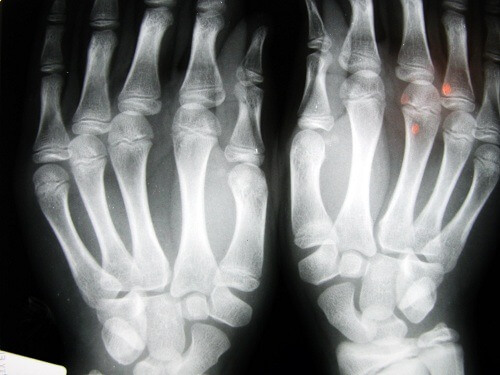

このトピックに関する最もよく知られている研究の一つは、ドナルド・アンガー博士が行ったもので、彼は60年以上、一日二回左手の指の関節を鳴らし、右手では行いませんでした。毎年、彼は手の検査をしましたが、どちらの手にも、変性疾患は現れませんでした。

別の研究では、ロサンゼルスの特別養護老人ホームで30人の高齢者を対象に調査が行われましたが、人生でずっと指の関節鳴らし行っていた人たちの間でも、変形性関節症はありませんでした。第三の研究は、デトロイトで45歳の人を対象に行われましたが、主な問題は握力が低下していたことと、その80%以上が手の腫れに悩まされていることでした。